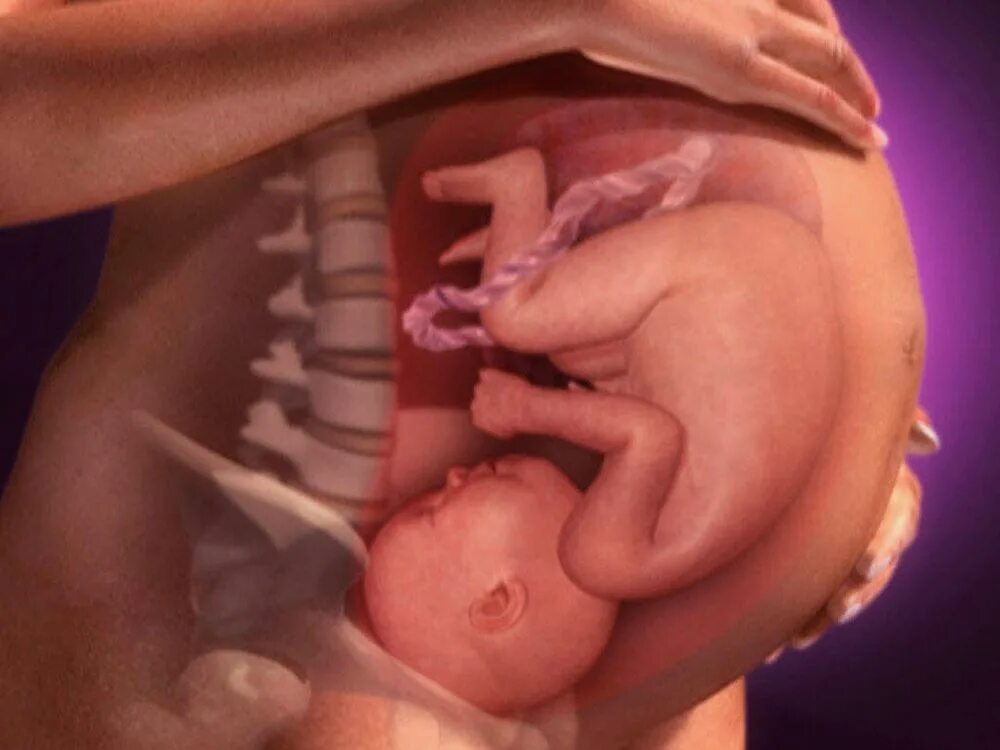

37 неделя беременности что происходит с малышом